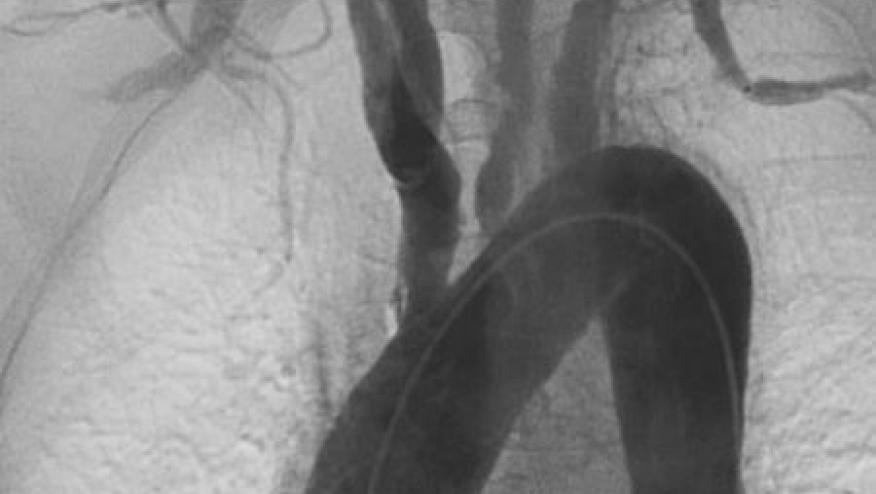

A Cleveland Clinic review of patients undergoing thoracic aortic surgery (1996‐2012) identified 196 patients with histopathology‐proven non‐infectious aortitis. The majority of these patients had a recognized systemic disorder, and serial assessments and imaging is crucial to an accurate diagnosis.

The majority of patients (66%) with histopathology‐proven aortitis have CIA at the time of surgery. CIA patients infrequently report new symptoms over time, but new vascular lesions requiring surgery commonly occur.

Long term follow‐up (including large vessel imaging) is strongly advised for all aortitis patients.